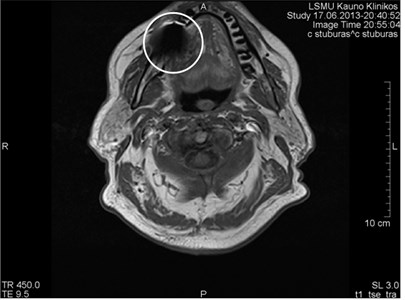

هل حشوات الأسنان آمنة للتصوير بالرنين المغناطيسي؟

نظرا لأن بعض حشوات الأسنان تحتوي على معدن ، يبدو أنها يمكن أن تسبب مشكلة في الجهاز. بعد كل شيء ، يمكن للمغناطيس تحريك الأجسام المعدنية. في الواقع ، حشوات الأسنان ، حتى المعدنية منها ، آمنة مثل أي مادة غير معدنية ولا داعي للقلق بشأنها